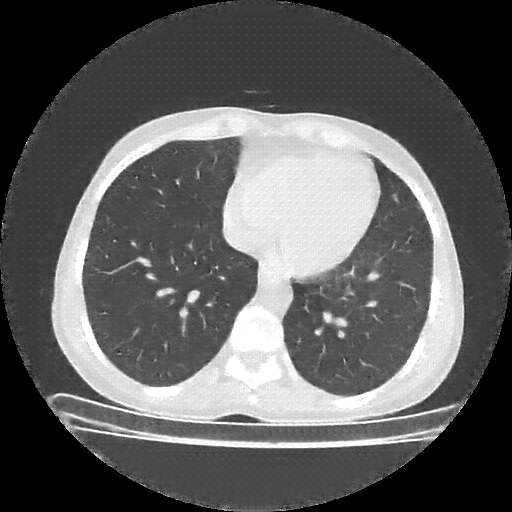

Original VENOUS CT scan

Lung window (WL -600, WW 1500 β†’ Low βˆ’1350, High +150)

Actual HU range: [-1350.0, 150.0]